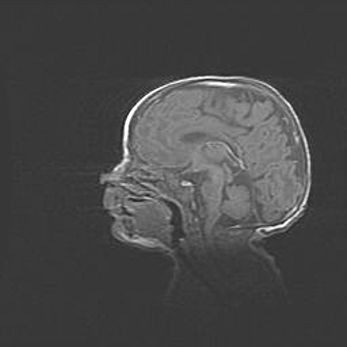

Неполная лизэнцефалия (пахигирия). Открытая гидроцефалия.

Возраст: 17 дней

Вес: 3110 г

Пол: мужской

Окружность головы: 33,5 см

Срок гестации: 35-36 недель

Лизэнцефалия—недоразвитие корковой пластинки и мозговых извилин в результате нарушения миграции нейронов коры. Поверхность мозговых полушарий гладкая. Микроскопически выявляется отсутствие нормальных слоев коры и скопление групп нейронов в подкорковом белом веществе.

Пахигирия—уменьшение числа вторичных извилин. В пораженном полушарии нервные клетки образуют толстый недифференцированный слой с неправильно расположенными нервными волокнами и группами гетеротопных клеток. Нервные клетки незрелые. Белое вещество истончено. При этом нередко аномально развит корково-спинномозговой путь.